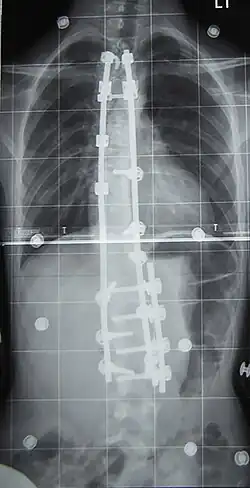

Surgery is usually recommended by orthopedists for curves with a high likelihood of progression (i.e., greater than 45–50° of magnitude), curves that would be cosmetically unacceptable as an adult, curves in people with spina bifida and cerebral palsy that interfere with sitting and care, and curves that affect physiological functions such as breathing.[104][105]

Surgery is indicated by the Society on Scoliosis Orthopaedic and Rehabilitation Treatment (SOSORT) at 45–50°[4] and by the Scoliosis Research Society (SRS) at a Cobb angle of 45°.[106] SOSORT uses the 45–50° threshold as a result of the well-documented, plus or minus 5° measurement error that can occur while measuring Cobb angles.[106]

Surgeons who specialize in spine surgery perform surgery for scoliosis. To completely straighten a scoliotic spine is usually impossible, but for the most part, significant corrections are achieved.[107]

The two main types of surgery are:[108]

- Anterior fusion: This surgical approach is through an incision at the side of the chest wall.

- Posterior fusion: This surgical approach is through an incision on the back and uses metal instrumentation to correct the curve.

One or both of these surgical procedures may be needed. The surgery may be done in one or two stages and, on average, takes four to eight hours.

In the 1980s, Cotrel–Dubousset instrumentation improved fixation and addressed sagittal imbalance and rotational defects unresolved by the Harrington rod system. This technique uses multiple hooks with rods to give stronger fixation in three dimensions, usually eliminating the need for postoperative bracing.[120]